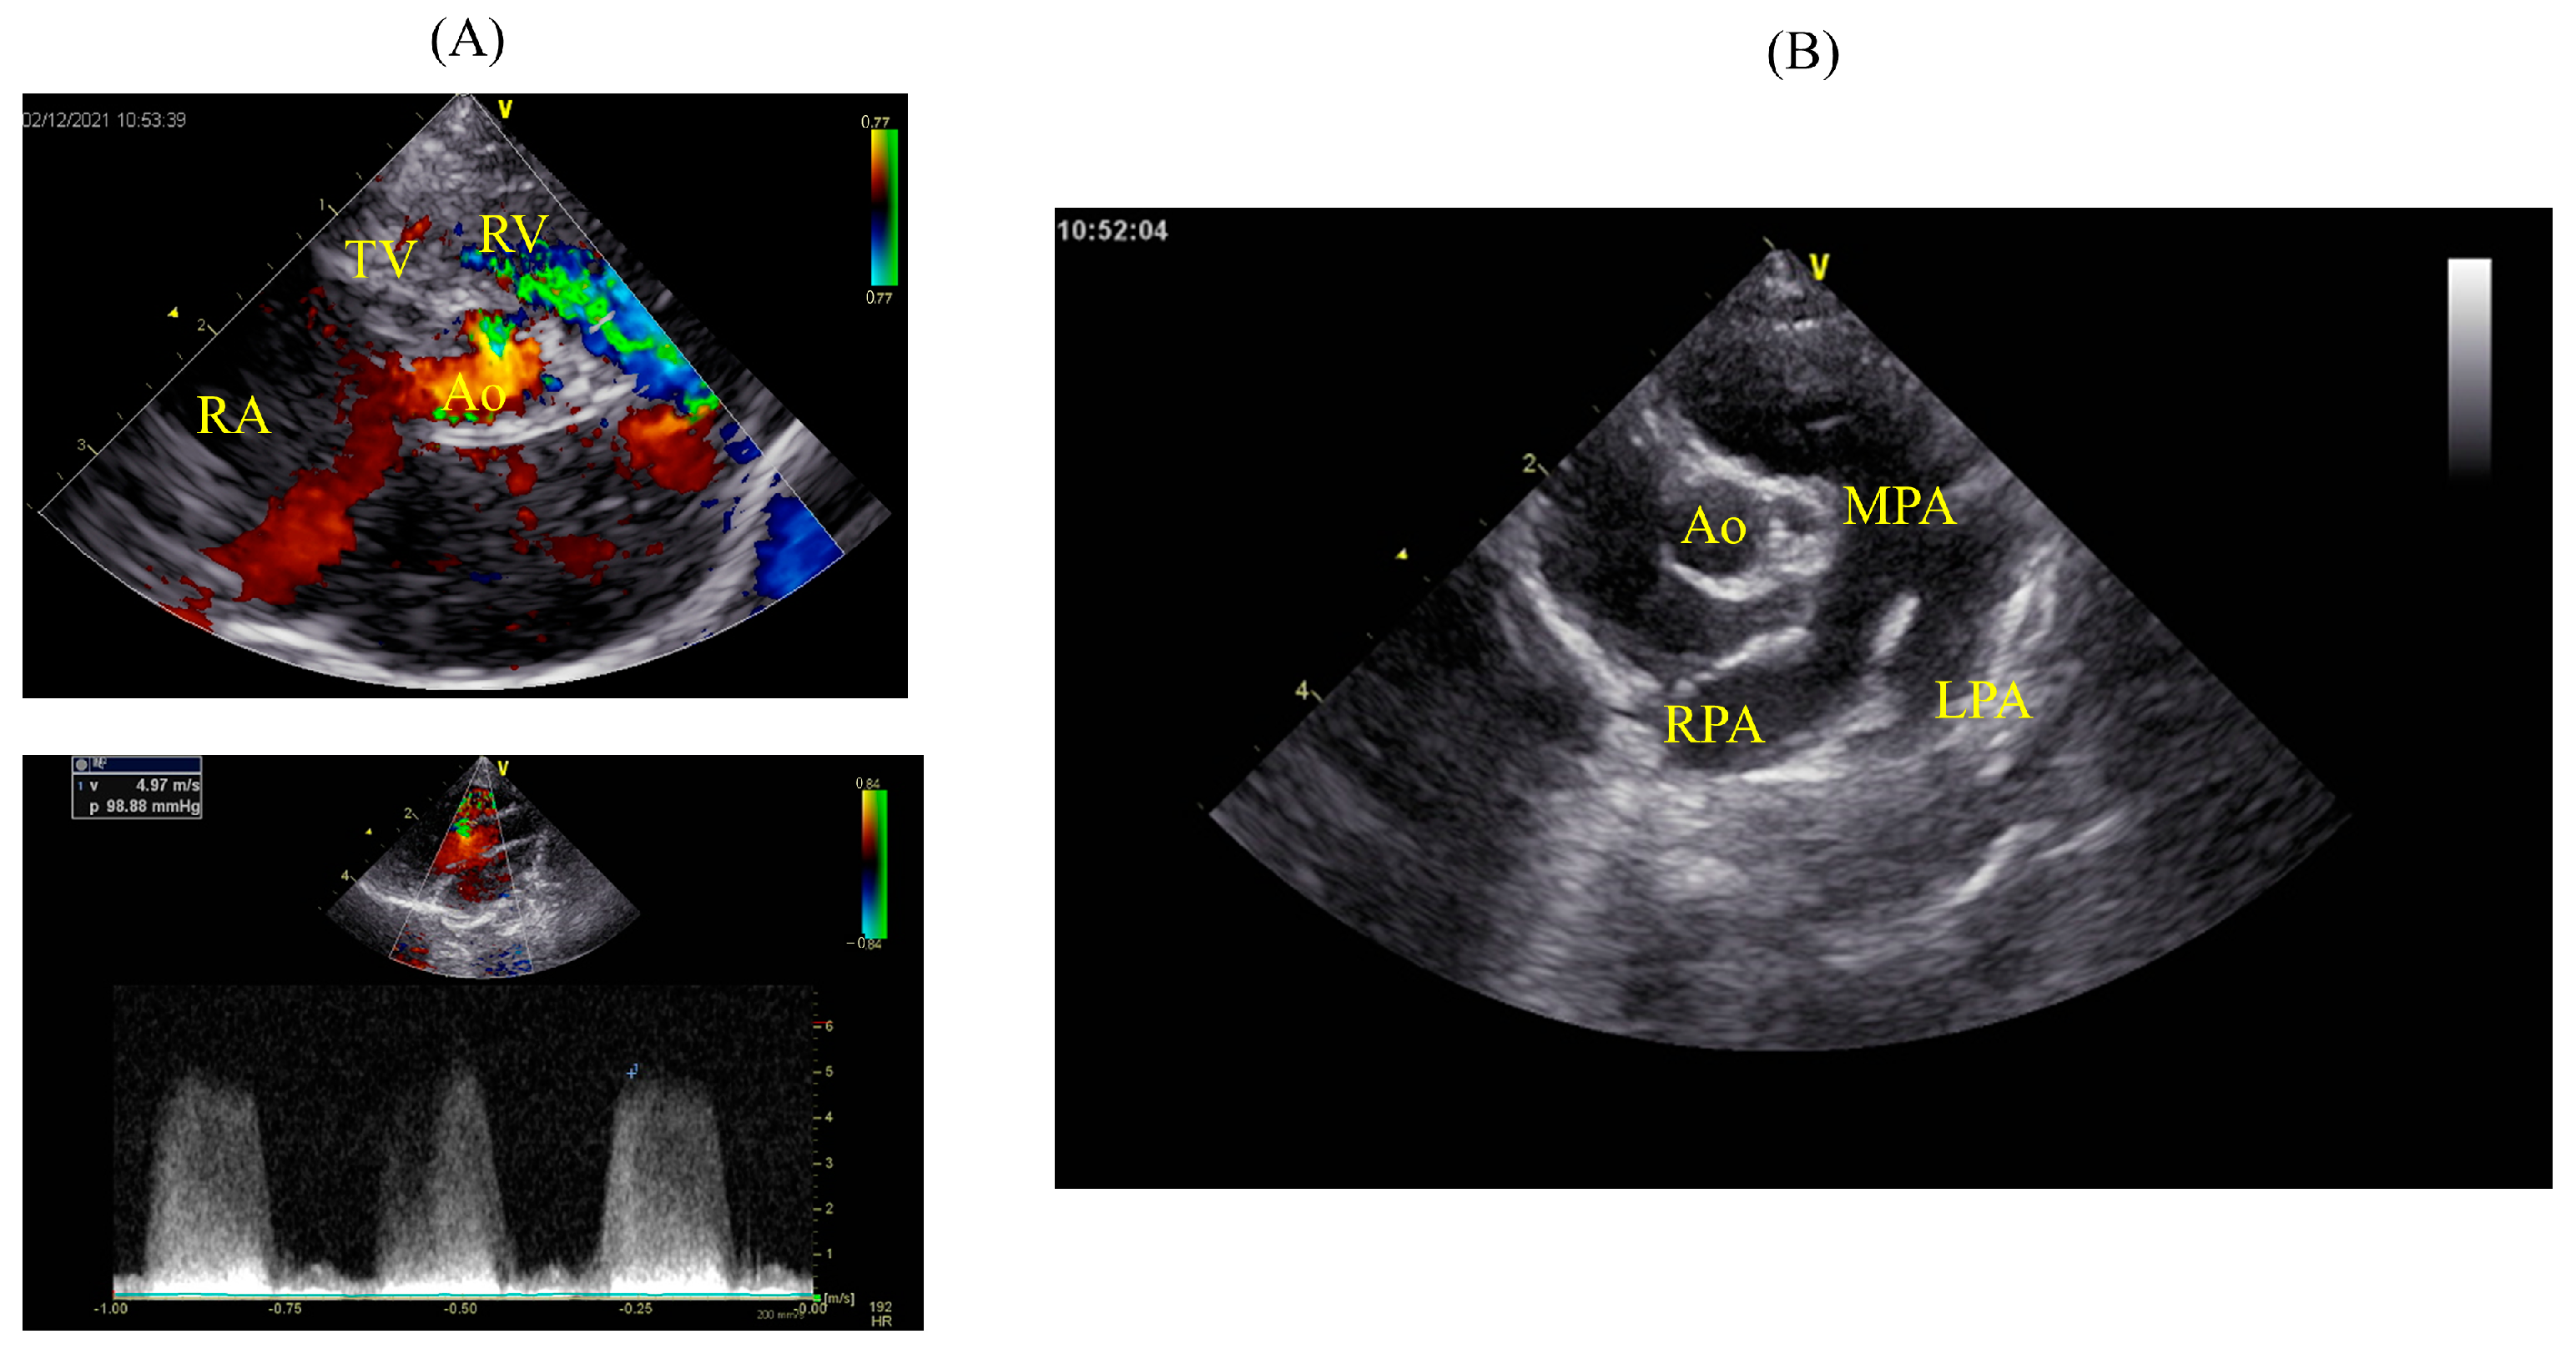

2. Case Description

2.1. Patient

2.2. Treatment